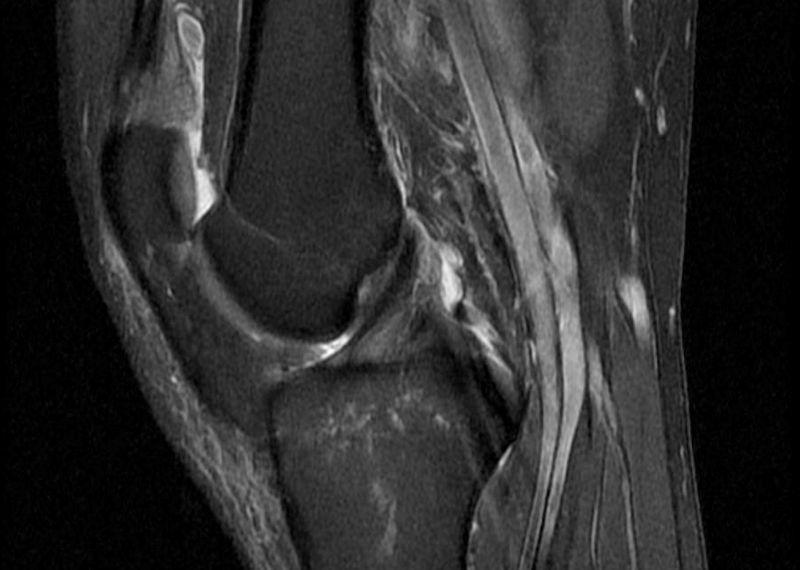

Tekom diagnostike se zmeraj poslužujemo magnetno-resonančnega slikanja, saj nam le-to potrdi poškodbo križne vezi in pokaže tudi morebitne dodatne poškodbe v kolenu.